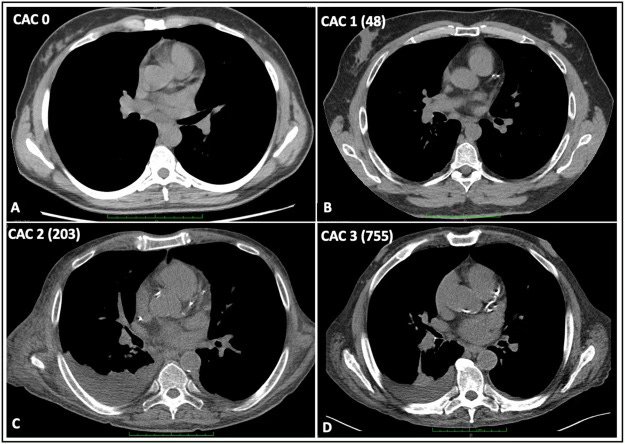

CT Coronary Artery Calcium (CAC) Scan

CT Coronary Angiogram (CTCA).

The CAC scan looks for deposits of calcium in the areas of the coronary arteries as a proxy marker for plaque.

It tells you ‘if’ there is plaque and how much, as a score called a CAC score.

When this scan is normal, the result is a CAC score of 0.

With a CAC score of 0, there is no advanced calcified plaque, and the risk of having a heart attack over the next ten years is in the range of 2%.

So a very low chance.